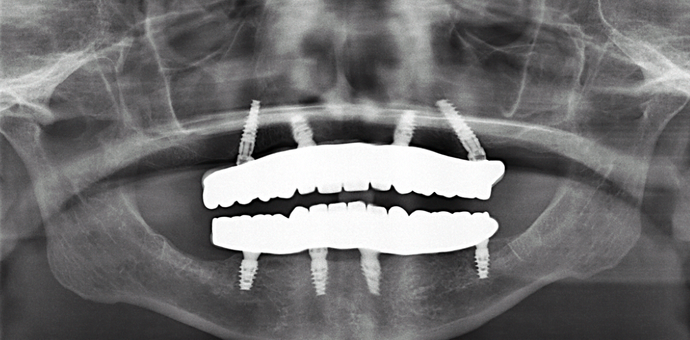

This retired professional had really healthy teeth until she was placed on several medications which caused dry mouth and quickly deteriorated her teeth beyond repair. She was extremely dissatisfied with her smile and wanted the best possible result. She had been offered snap on implant dentures by multiple dentists but she disliked the idea of removing her teeth at night and was therefore treated with full arch fixed bridges supported by implants all done in one day!

Procedures : extractions, implants, All on 4 , Teeth in a day, no bone grafting and full mouth reconstruction with monolithic zirconia bridges.

Testimonial : "Dr.Bidra you have made my dream smile come true! Now I can eat and enjoy the foods that I want without worrying about my teeth breaking or causing pain. This has been such a blessing and I highly recommend you and treatment to anyone out there”